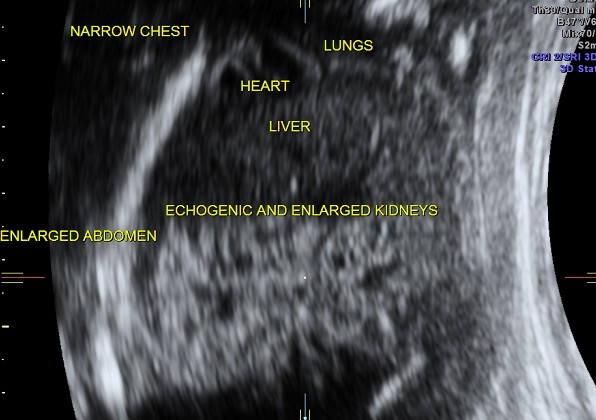

enlarged and hyperechoic kidneys

narrow , bell shaped chest , suggestive of pulmonary hypoplasia